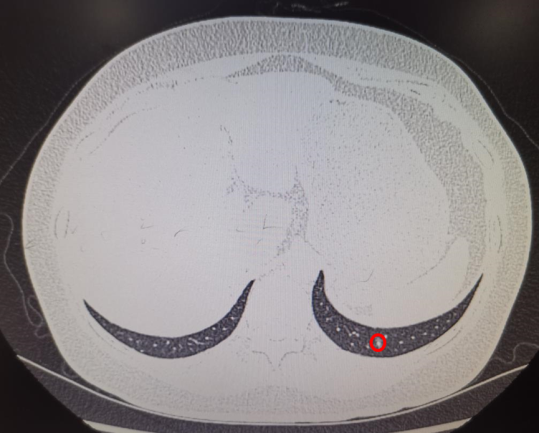

2例ENB下肺外周磨玻璃样结节(GGO)术前定位,难度大,尤其是患者肺GGO位于左肺下叶后基底段紧靠膈面,大小约0.6mm,常规CT引导下定位准确性极低。在电磁导航支气管镜引导经肺实质结节通道技术(ENB-TPNA)支持下准确定位,并行微创肺楔形切除术。

ENB-MWA患者术前小结节位置及消融术后3天复查CT见病灶区域成消融后炎性改变(完全覆盖结节位置)。